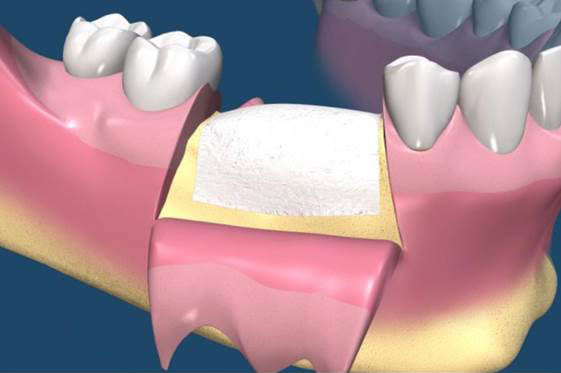

在 GTR 及 GBR 技術中所使用的阻隔膜是用來將缺損的區域分開成兩個隔間。 GTR 技術的目的是再生完全俱功能的牙周膜,包含新的牙骨質、牙周韌帶(PDL)及新骨。GBR 技術的目的是再生新骨,對此,細胞從下層的骨組織需要分佈至缺損處。(圖09-12)

圖09

圖10

圖11

圖12